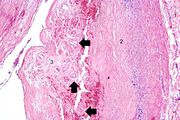

| 16:28, 19 August 2013 | IPLab4MuralThrombus3.jpg (file) | 53 KB | Seung Park | This higher-power photomicrograph shows the border between the thrombus on the right (1) and the endocardium on the left (2). There is a line of inflammatory cells at this interface (arrow). | 1 | |